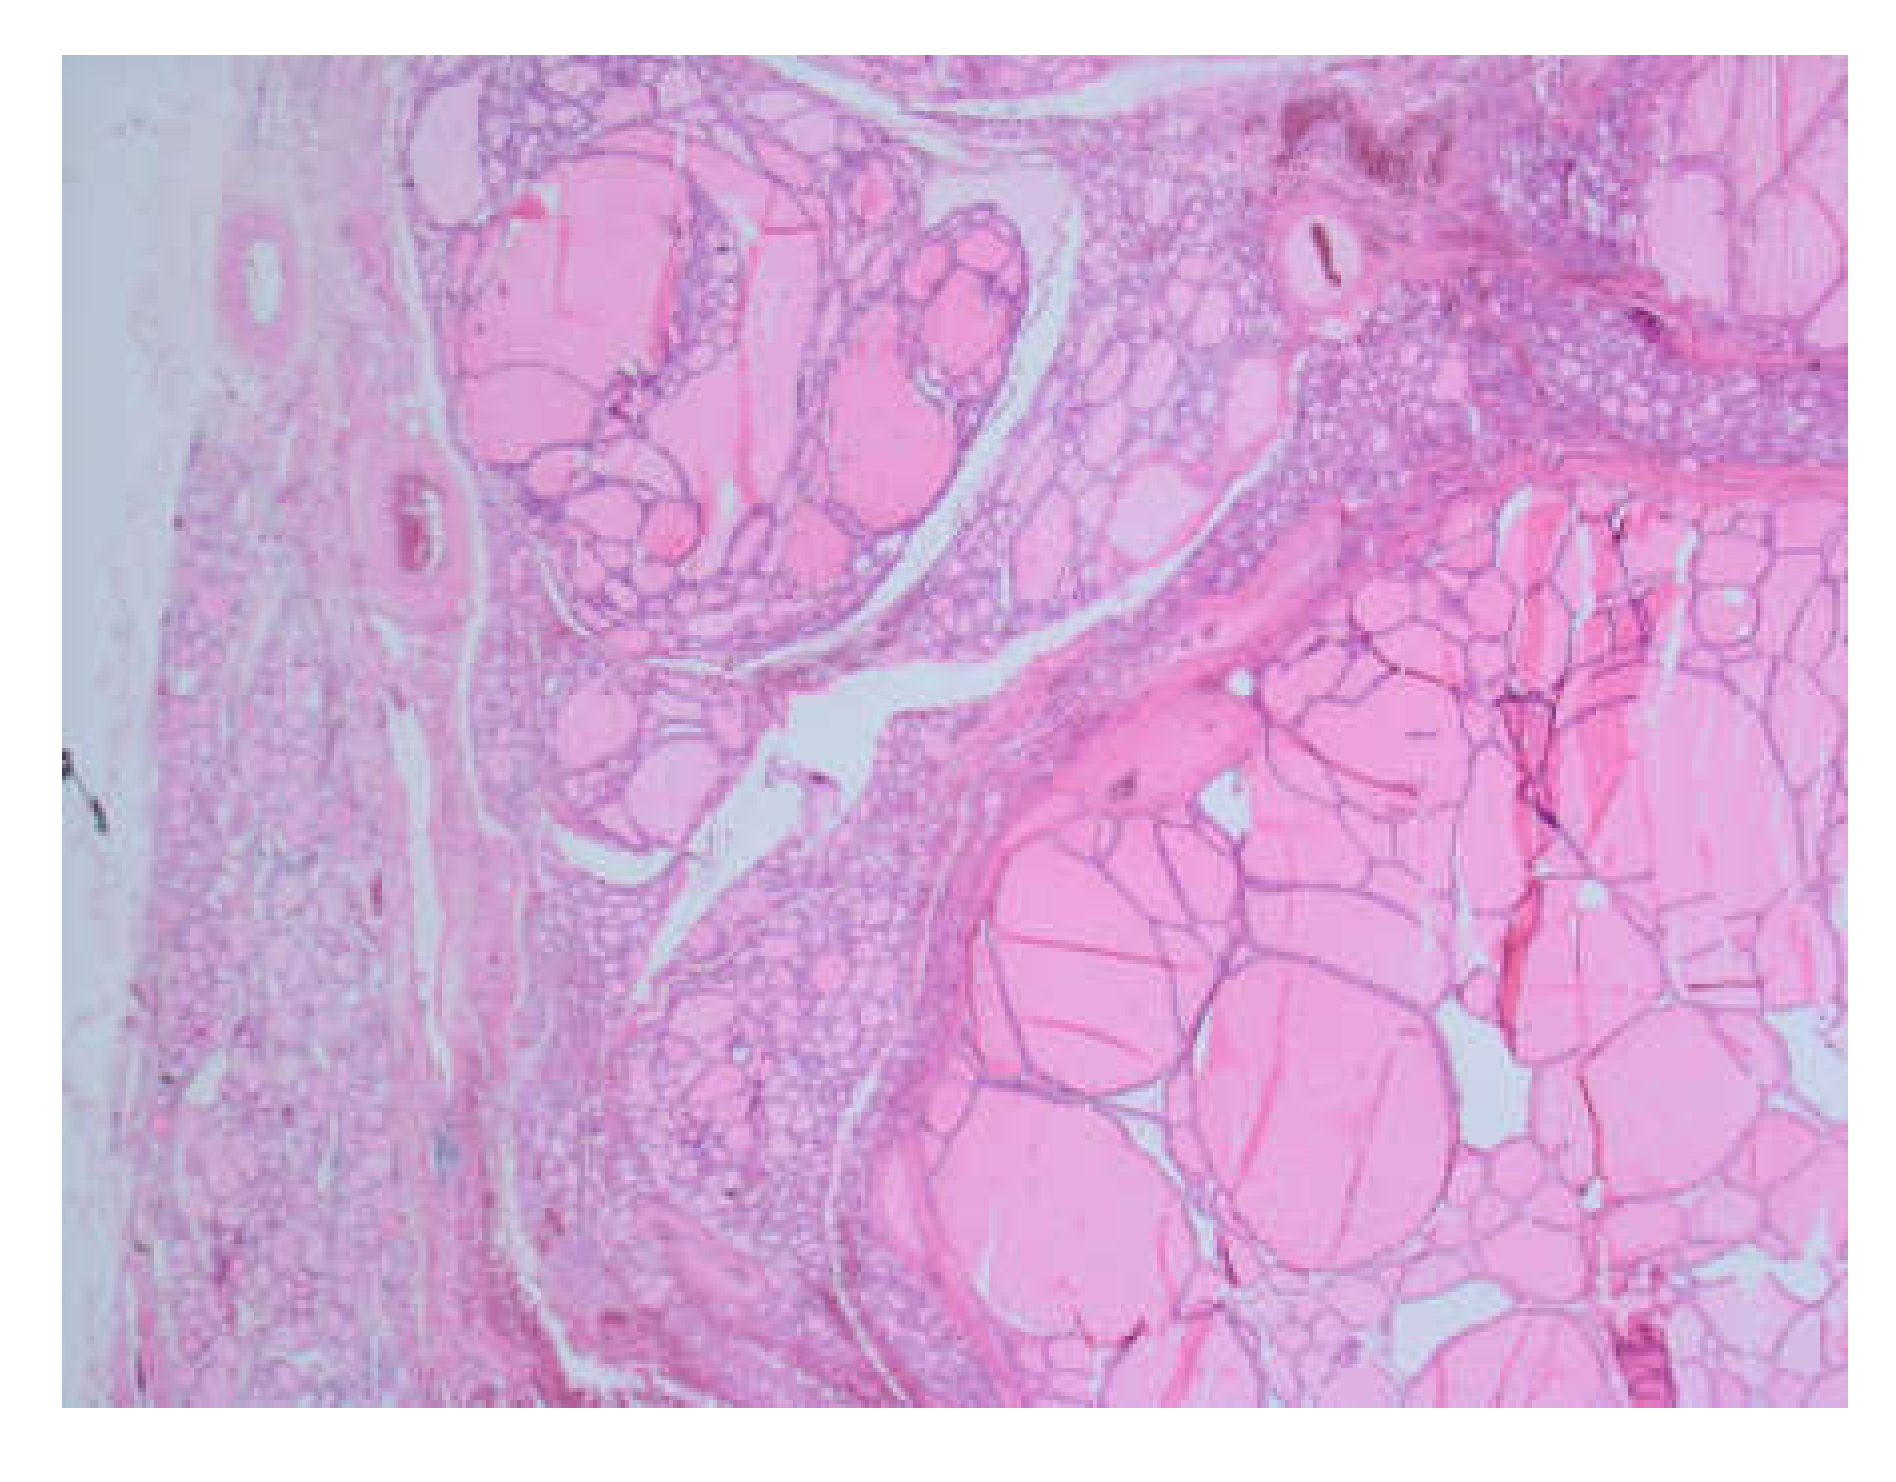

2. Case Presentation